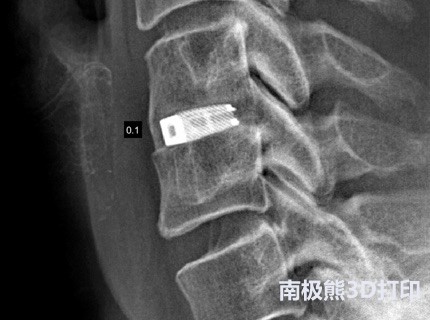

总部位于德国Wurmlingen的EIT是一家私人控股的3D打印钛椎体植入物制造商,用于脊柱融合手术。 该产品利用EIT专有的先进技术,其由开放且互连的多孔结构组成,旨在使骨骼生长到植入物中。 这些技术将通过强生医疗器械公司的商业基础设施提供给世界各地的患者。

此次收购使强生公司的整形外科业务DePuy Synthes能够增强其全面的椎体间植入物产品组合,包括可扩展的椎体间装置,钛合金PEEK技术和现在的3D打印蜂窝钛。 EIT技术旨在补充DePuy Synthes对微创和开放式脊柱手术的椎间植入部分的关注。